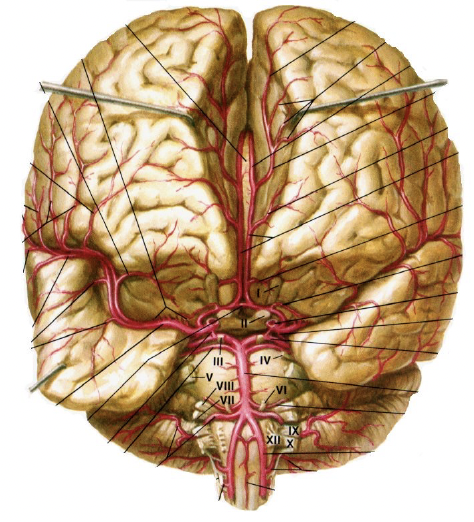

21

Q

ID the structures

A

22

ID the vessels